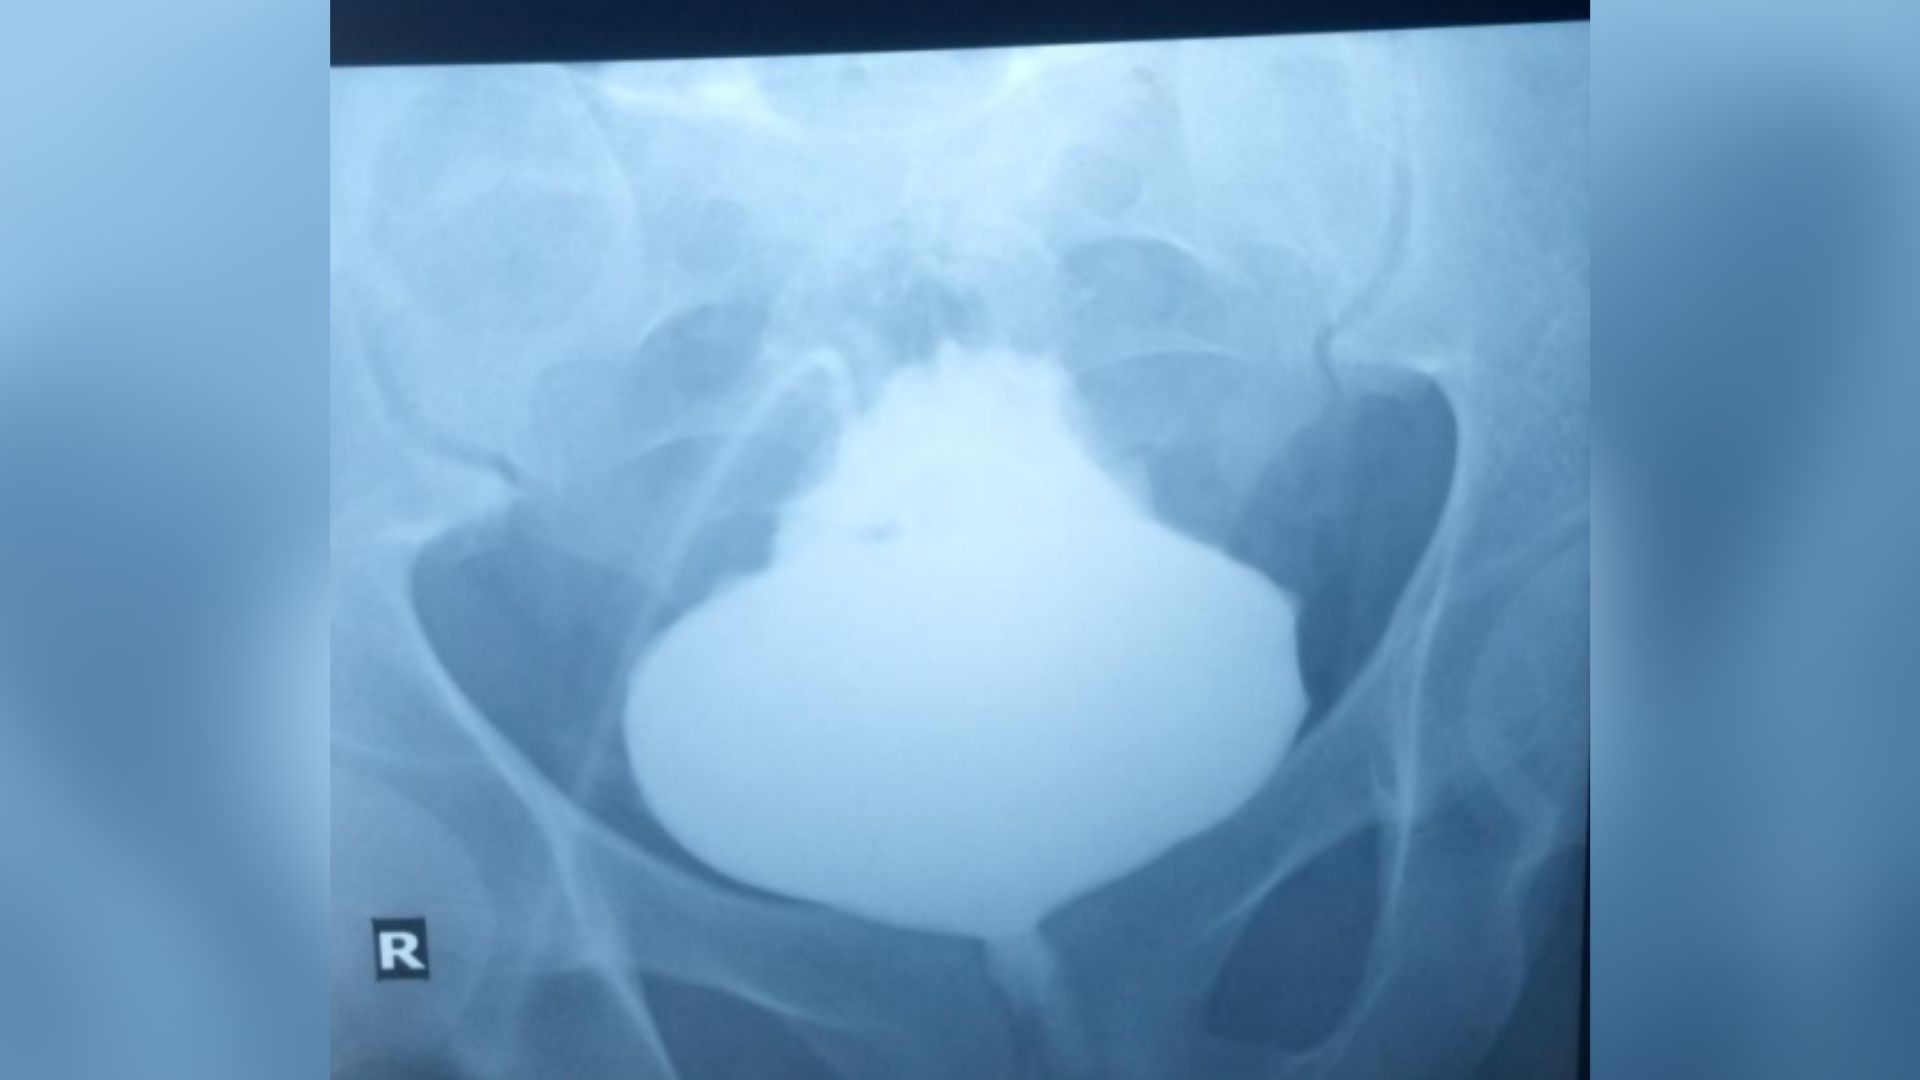

medical image of a man's pelvis with full bladder shown in the center

Les médecins ont orienté le patient vers le service de radiologie pour effectuer des scans de sa vessie et rechercher des signes de telles anomalies physiques. Pour visualiser la vessie sur les radiographies, les radiologues ont administré un colorant sensible aux rayons X à travers le cathéter abdominal. Cela a révélé que la vessie s’était gonflée à sa base, laissant une pointe pointue.

Le diagnostic : Cette condition est connue sous le nom de vessie « arbre de Noël » ou « pomme de pin », en raison de son apparence.

Les radiographies ont confirmé que l’urine ne pouvait plus quitter l’organe. Pourtant, une inspection plus approfondie de la vessie n’a révélé aucun problème avec l’organe lui-même, comme une masse obstructive ou des calculs vésicaux. Cela a amené les médecins à se demander si une obstruction se trouvait ailleurs.